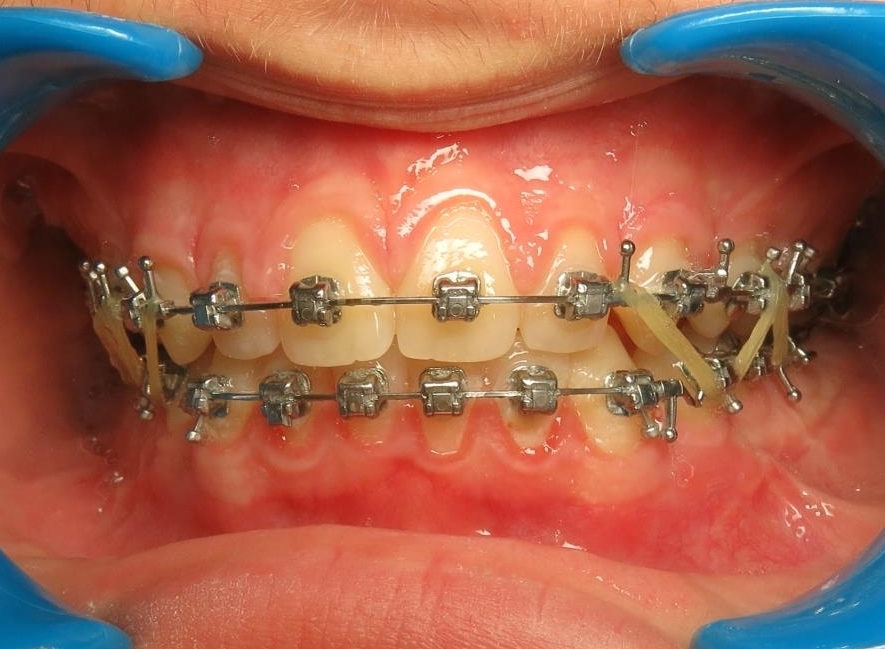

2 - Préparation orthodontique et résultat après chirurgie

Les photos supérieures montrent les arcades juste avant la chirurgie, avec un alignement complet et des axes dentaires physiologiques. La largeur de l’arcade maxillaire a été préparée pour permettre un emboîtement optimal après l’avancée mandibulaire. En bas, les photos post-opératoires montrent des arcades désormais coordonnées, avec une occlusion stable et harmonieuse, grâce à une préparation rigoureuse en amont de l’intervention chirurgicale.